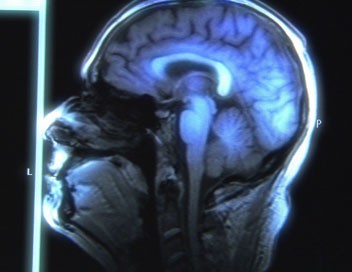

Je supprime la publicitéLes récentes recherches sur le cerveau ont mis en évidence ses incroyables capacités de réorganisation structurale et fonctionnelle. Après s'être penché sur la plasticité neuronale et ses effets possibles sur des handicaps physiques, le psychiatre Norman Doidge explore ici les implications de ces capacités d'adaptabilité dans le traitement des troubles mentaux. Du Canada à l'Espagne, il part à la rencontre de chercheurs qui pourraient révolutionner le quotidien des patients atteints de troubles obsessionnels compulsifs, de stress post-traumatique, d'aphasie ou de schizophrénie, et leur offrir un espoir de guérison.